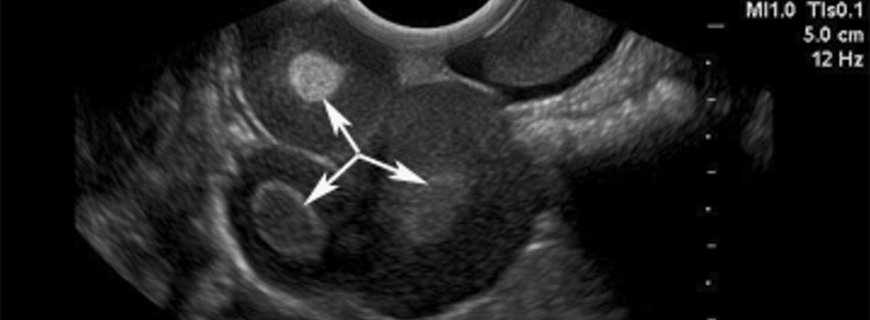

Struma Ovarii Nedir ve Neden oluşur?Struma ovarii tiroid dokusunun diğer elemanlardan fazla geliştiği ve baskın doku olduğu bir teratomdur. Yumurtalıkta tiroid dokusunun tümör benzeri büyümesidir, %2-3\'ü tek taraflıdır ve çapları 10 cm\'den azdır. B...